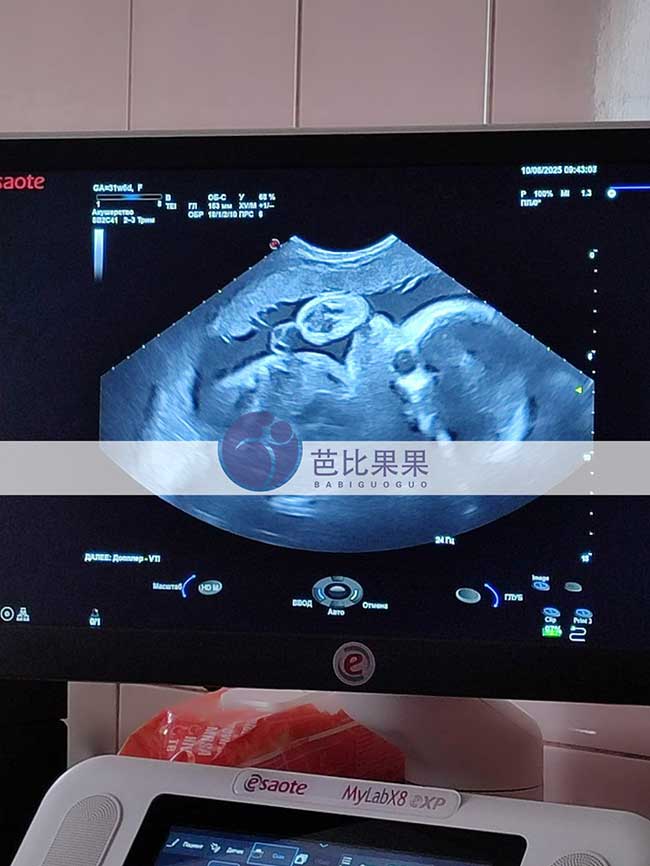

宋先生在乌克兰分配的试管妈妈做孕31周+B超产检,胎宝宝发育很健康。